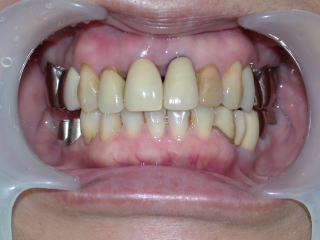

右下5番6番を装着しました。

予定外の手前5番脱離もありましたが、患者さんには大満足していただけました。